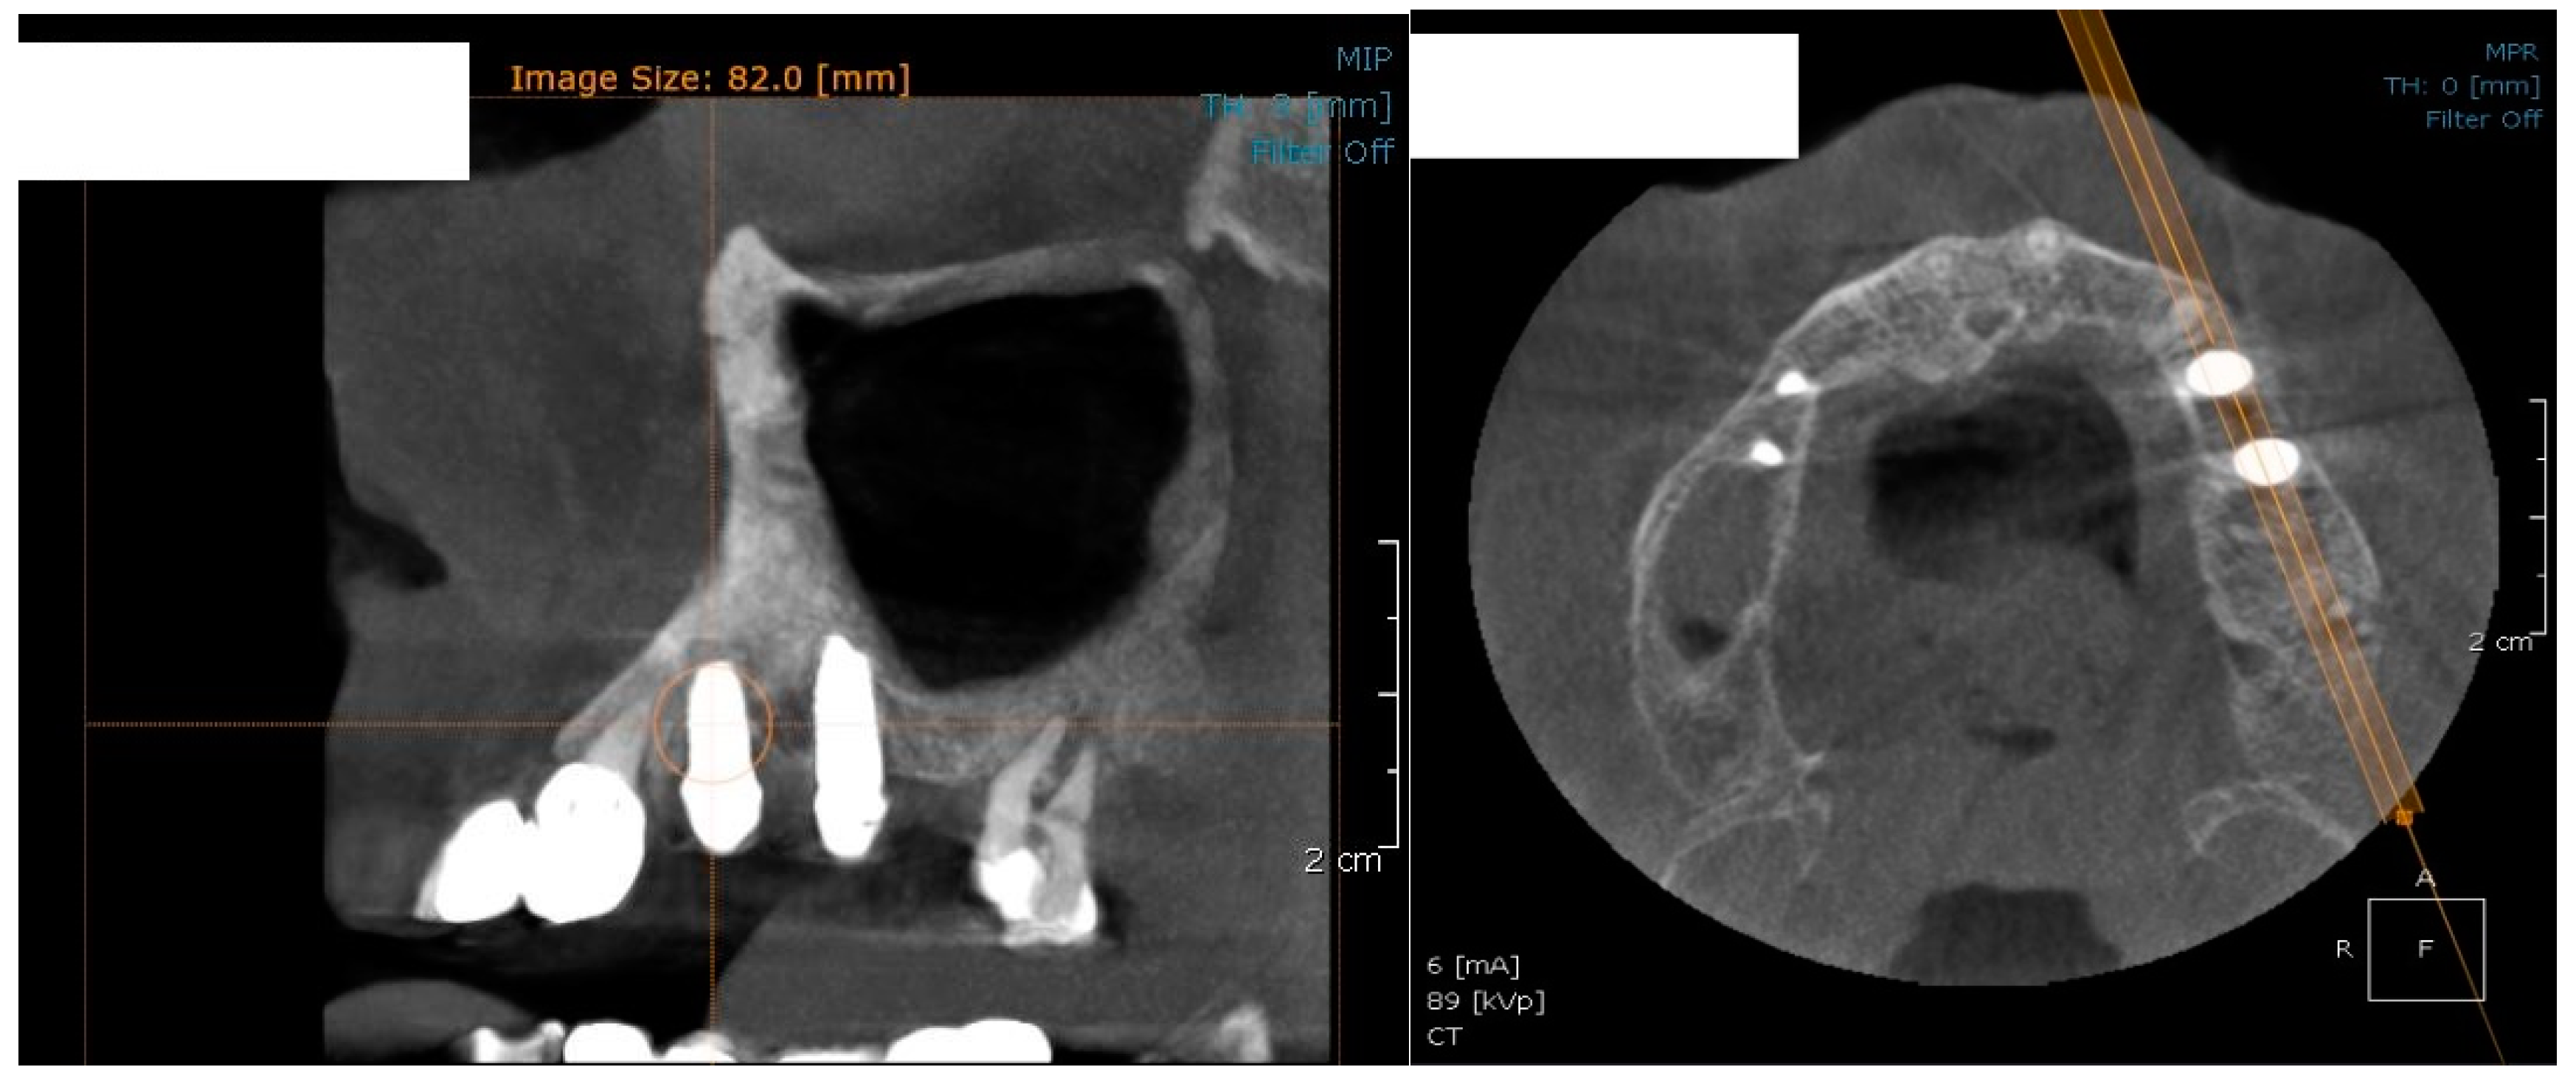

In the subsequent stage of the study, the clinical objectives were met, namely the determination of the radiological bone level, width, height and bone density on Cone Beam Computed Tomographyscans (Planmeca™, Helsinki, Finland). CBCT images were recorded using a tube voltage of 89 kV and a current intensity of 6 mA, the images were recorded with a cylindrical field of view (FOV) of 82 mm both in diameter and height (Figure 1), the voxel size was 0.2 × 0.2 × 0.2 mm and the dental arches were positioned similarly in the FOV, as presented in Figure 2.

Figure 1.

The field of view was a cylinder of 82 mm in diameter and height. The left panel is a 3D section CBCTCone Beam Computed Tomography image, whereas the right panel represents an oblique-section of the same image. F, frontal view, A, Axial View, R, right side view.